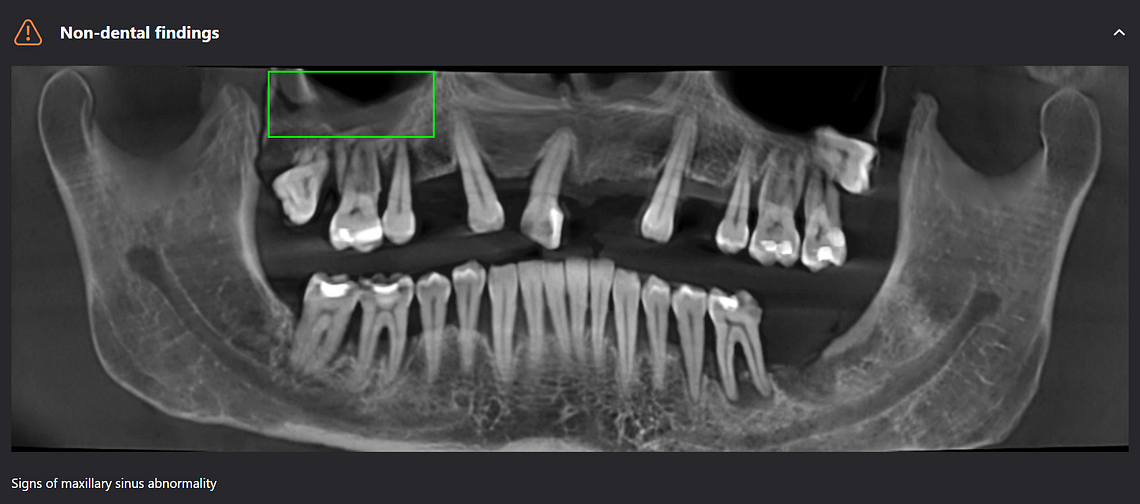

Panoramic radiological report

Diagnocat can pick up non-dental pathology as well, such as thickening of the sinus lining and bone cysts.